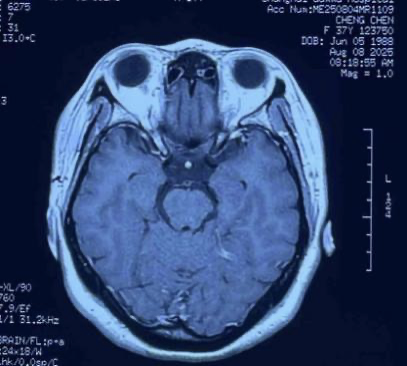

A female patient presented with a brainstem glioma, experiencing two months of weakness while walking and numbness in her right limbs. MRI revealed a tumor in the left brainstem, and pathology confirmed a brainstem glioma.

More than four years later, the patient remains in excellent condition, leading a normal life and working without restrictions. Dr. Wang emphasized the importance of regular MRI follow-ups. If small recurrences are detected, timely CyberKnife treatment can control progression. At her latest MRI check in August, the tumor had significantly shrunk.